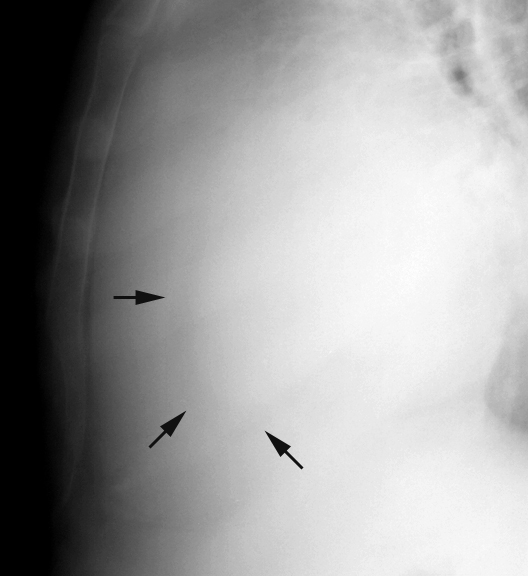

Peric effusion c/u